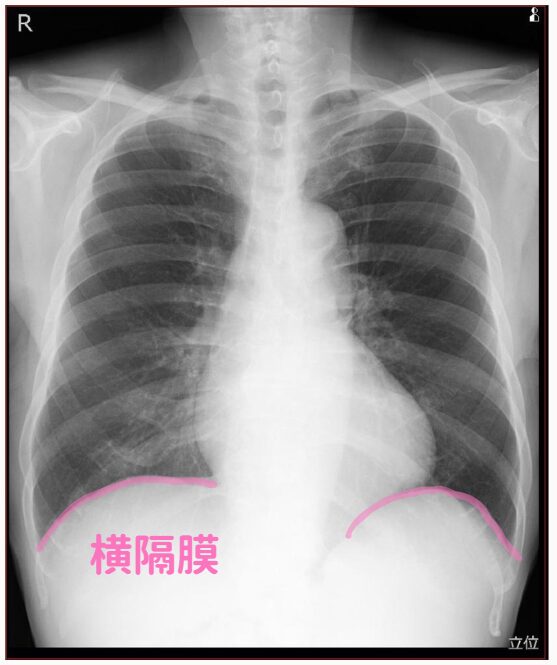

(8)横隔膜

最後に横隔膜も見ます。

ちなみに、横隔膜は右側がちょっと上にあるのが正常です。

理由は肝臓があるからです。